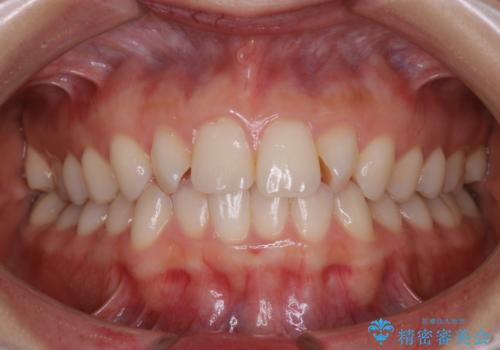

30代女性 前歯のがたつき

![[ 前歯のガタつきを治す ]マウスピース矯正インビザラインの症例 治療前](https://seimitsushinbi.jp/wp/wp-content/uploads/2022/01/IMG_0237-500x350.jpg?v=1642039695)